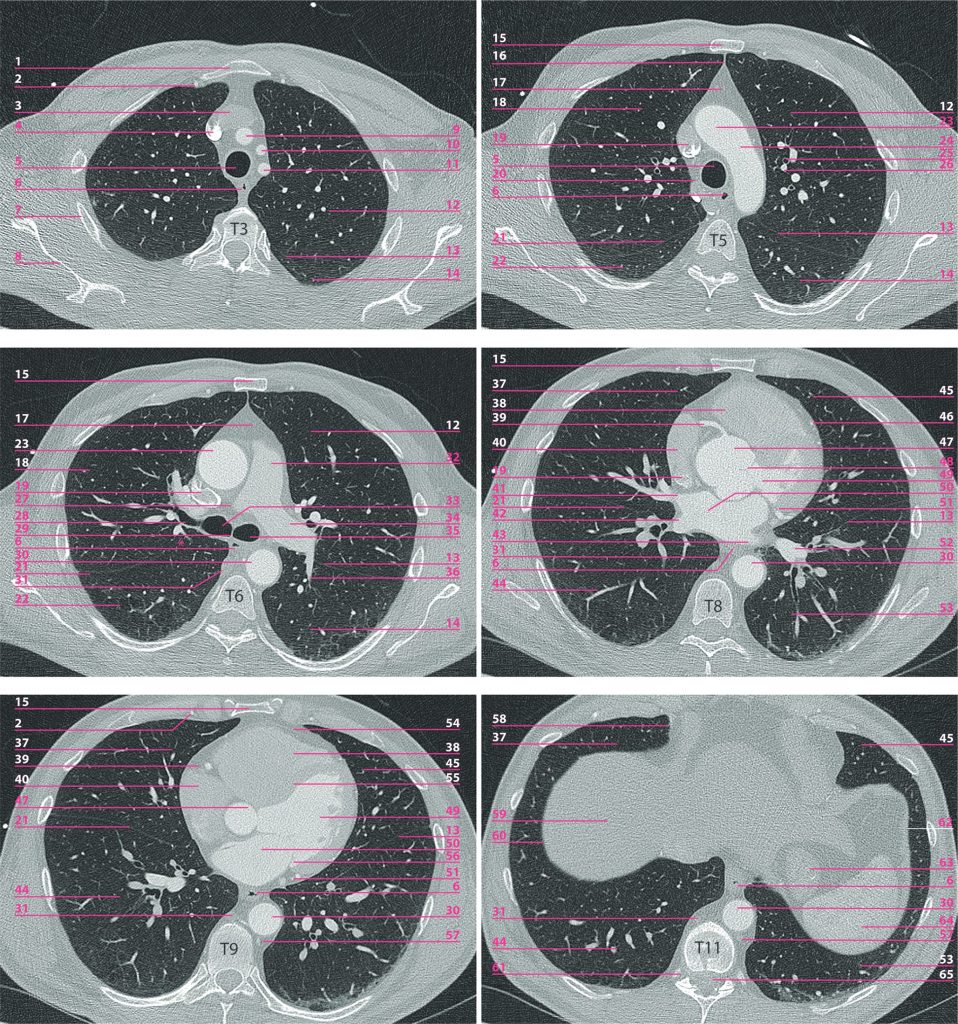

Fig. 89.2 Coupes horizontales de scanner.

Le niveau de la coupe est indiqué par la vertèbre. Sur la coupe par T6, l’astérisque indique une interruption de la grande scissure droite (scissure incomplète, variante de la normale).

1. Manubrium sternal. 2. Pédicule thoracique (mammaire) interne droit. 3. Veine brachiocéphalique gauche. 4. Veine brachiocéphalique droite. 5. Partie thoracique de la trachée. 6. Partie thoracique de l’œsophage. 7. Arc costal moyen. 8. Scapula droite. 9. Tronc brachiocéphalique. 10. Artère carotide commune gauche. 11. Artère subclavière gauche. 12. Lobe supérieur du poumon gauche (culmen). 13. Grande scissure gauche. 14. Lobe inférieur du poumon gauche (segment apical — segment 6 dans la classification de Boyden). 15. Corps sternal. 16. Ligne médiastinale antérieure (affrontement du bord antérieur des poumons). 17. Loge thymique (médiastin antérieur). 18. Lobe supérieur du poumon droit. 19. Veine cave supérieure. 20. Crosse de la veine azygos. 21. Grande scissure droite. 22. Lobe inférieur du poumon droit (segment apical, 6). 23. Aorte ascendante (segment 1). 24. Arc aortique (segment 2). 25. Bronche distale du territoire de la bronche apicale du lobe supérieur gauche (normalement de diamètre inférieur à l’artère satellite). 26. Artère distale du territoire de l’artère apicale du lobe supérieur gauche. 27. Artère pulmonaire droite. 28. Bronche lobaire supérieure droite. 29. Bifurcation trachéale et carène. 30. Aorte thoracique descendante (segment 3). 31. Veine azygos. 32. Tronc pulmonaire. 33. Bronche principale droite. 34. Artère pulmonaire gauche. 35. Bronche principale gauche. 36. Artère du segment apical du lobe inférieur gauche. 37. Lobe moyen du poumon droit. 38. Ventricule droit. 39. Artère coronaire droite. 40. Atrium droit. 41. Veine pulmonaire supérieure droite. 42. Veine pulmonaire inférieure droite. 43. Veine pulmonaire inférieure gauche. 44. Lobe inférieur du poumon droit (pyramide basale). 45. Lobe supérieur du poumon gauche (lingula). 46. Artère interventriculaire antérieure et grande veine du cœur. 47. Sinus aortique (segment 0). 48. Valve aortique. 49. Ventricule gauche. 50. Atrium gauche. 51. Artère circonflexe. 52. Veine pulmonaire inférieure gauche. 53. Lobe inférieur du poumon gauche (pyramide basale). 54. Péricarde. 55. Septum interventriculaire. 56. Feuillet latéral de la valve mitrale (petite valve mitrale). 57. Veine hémi-azygos. 58. Angle cardiophrénique droit. 59. Dôme hépatique (segment VIII). 60. Coupole diaphragmatique droite. 61. Foramen intervertébral T11-T12 droit. 62. Coupole diaphragmatique gauche. 63. Estomac (fundus). 64. Rate. 65. Canal vertébral et moelle spinale.

Source : CERF, CNEBMN, 2022.